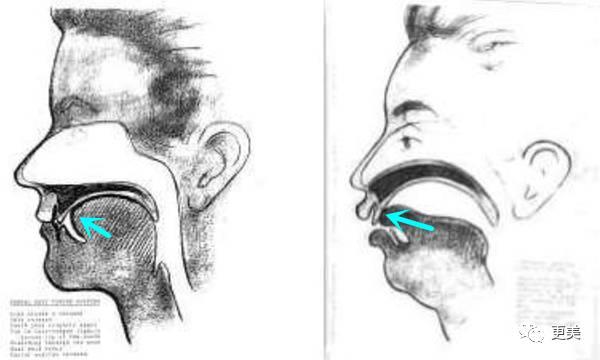

正确的呼吸是空气经由鼻腔到达气管,大概是这个路线

但许多人的呼吸习惯是经由口腔进入气管,舌头不再紧贴上颚,后果很明显

1。舌头位置向下压,口腔的空间就变大了,舌尖顶到牙齿,导致牙齿一直受到向外的力,慢慢形成牙凸

2。口腔空间变大,双下巴就形成了

呼吸导致的牙性、骨性畸形,是从孩童时期就开始的,所长找了两个案例来说明呼吸引起的嘴凸